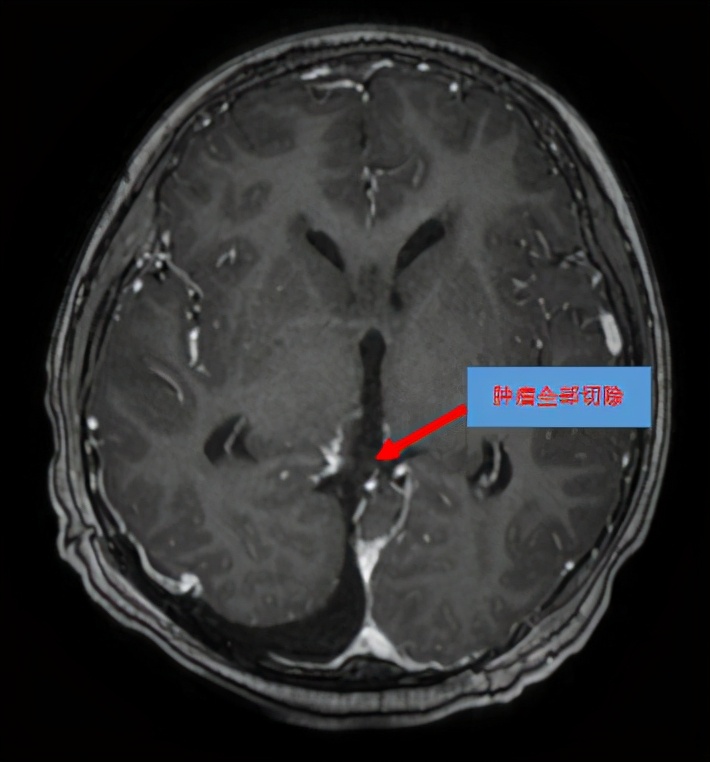

在做好充分术前准备之后,神经外科陈陆馗主任团队于2月22日给民仔进行了枕部开颅松果体区及第三脑室后部肿瘤切除术,肿瘤切除后,完全恢复了脑脊液循环通路,拔除了脑室引流管。病理报告显示是混合型生殖细胞肿瘤。

图片说明:术后MR显示松果体区及第三脑室后部肿瘤已全切。

“现在躺在病床上不敢玩手机了,以后也不敢玩了。”目前民仔病情较前明显好转,已无任何头痛、呕吐等不适,他深刻认识到玩游戏的危害。